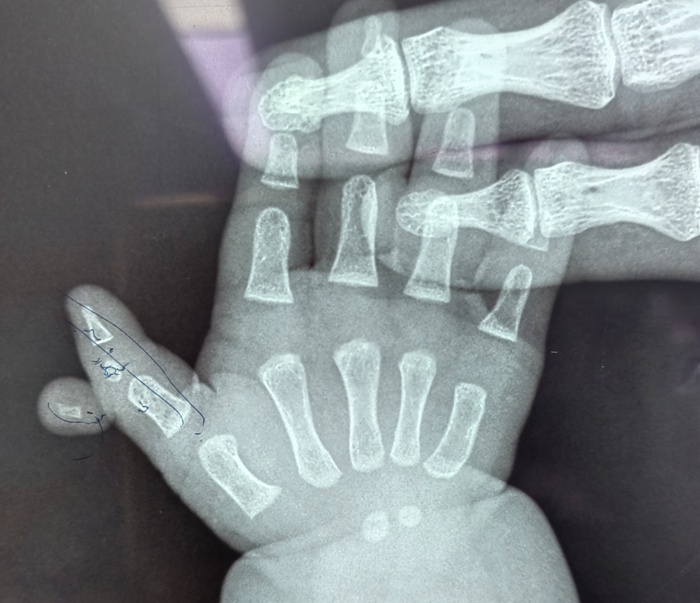

近日,在蜜桃视频 的手术室内,一场特殊的手术正在进行。手术台上,一位仅六个月大的女婴安静地躺着,她的右拇指旁多出一个发育不全的指节,这个多余的手指像影子一样跟随着拇指移动,同时右拇指又长又歪,虽然不影响生命,但却严重影响了患儿手部功能的正常发育。

据孩子的妈妈介绍,孩子一出生,他们便发现了异常,孩子右手拇指较正常手指明显歪斜并且比左手的拇指要长,且在这根手指外侧,还多出来一截手指。多余的手指长在拇指指间关节处,虽然有指甲、有手指形态,但因为发育不全而缺乏自主活动能力。考虑到孩子年龄太小,家长一直未敢轻易做出治疗决定。

手术当天,骨科医护人员制定了周密的手术方案。在精准地切除了多余的手指后,切除了Delta骨块,修复韧带并予克氏针固定,对畸形的拇指进行了矫正。最终,患儿的右拇指恢复了正常形态。术后,患儿在医护人员的精心护理下逐渐康复,小手也变得更加灵活。医护人员高超的技术和优质服务,也赢得了家长由衷的感谢。

据骨科主任高凤奇介绍,三节拇指合并多指畸形并不常见,正常的多指多在一周岁以后手术治疗,多指的切除相对简单,但是三节拇的矫形较为复杂。合并Delta骨块的三节拇指合并多指一定要早期治疗,最早可以在六个月即可手术,越早做手术效果越好,蜜桃视频 儿童骨科是长春市“十四五”医学重点专科,是吉林省内唯一一家专业的儿童骨科科室,历史悠久、综合实力雄厚。对于常见的儿童先天性肌性斜颈、多指、先天性髋关节脱位,以及复杂的四肢畸形、骨关节感染等有着丰富的治疗经验。